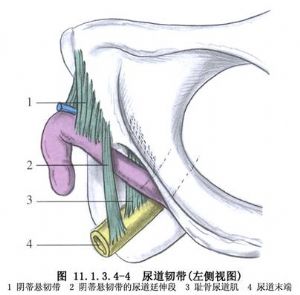

發生應力性尿失禁的原因約有:①位於膀胱頸部的內括約肌中兩組U字形平滑肌束,不能分別向尿道前、後收縮,因而關閉不住尿道;②外括約肌的橫紋肌層,在尿道中1/3段形成環狀括約肌,於膀胱內壓力升高時,不能增加張力,尿液即溢出;③肌肉,如恥尾肌、球海綿體肌;筋膜,如恥骨-膀胱-宮頸筋膜等,能保持膀胱和尿道的正常位置。如分娩損傷,肌肉及筋膜鬆弛,膀胱頸部脫垂,呈漏斗狀,易致應力性尿失禁;④正常時尿道後壁與膀胱三角底部呈90°~100°的鈍角,稱尿道后角。如膀胱、尿道周圍的肌肉、筋膜損傷、鬆弛,使尿道后角消失,這是尿失禁的重要原因(圖11.1.3.4-1~11.1.3.4-6)。